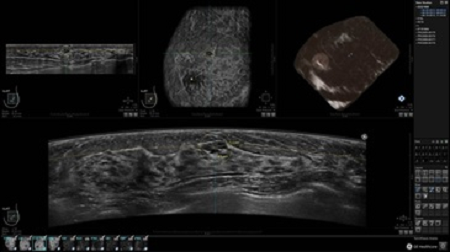

GE INVENIA ABUS – это современный УЗИ аппарат, который создан для точной и эффективной диагностики сканирования с высокой плотностью молочных желез. Выявляемость патологий раковых и предраковых стадий заболевания составляет 55%, что в конечном счете позволяет ставить врачу точные и своевременные диагнозы. Традиционные методы использования маммографии не показывают такой выявляемости, ограничиваясь лишь 3-38%.

УЗИ-аппарат GE INVENIA ABUS позволяет проводить максимально операторонезависимые процедуры, что значительно снижает риск неправильной постановки диагноза и сопутствующие издержки на обработку информации. Система готовит отчет в течение 3-х минут после сканирования, это безусловное преимущество по сравнению с обычным УЗИ сканером.

• Получение объемных 3D изображений с возможностью покадрового просмотра

• Получение изображений в поперечной плоскости (в реальном времени) и в коронарной плоскости (статическая, для указания нахождения соска)

• Отображение объемных 3D ультразвуковых изображений, которые состоят из традиционных поперечных и воссозданных коронарных и сагиттальных проекций

• Возможность отображения полного 3D изображения

• Стандартизованная ориентация изображения: «толстый срез» в коронарной плоскости; поперечная; сагиттальная плоскость; радиальный и антирадиальный поворот изображения; просмотр исключительно области интереса